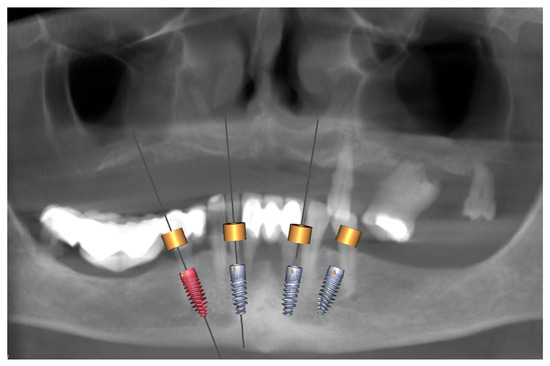

3.1. Planning and Preparation for the Treatment